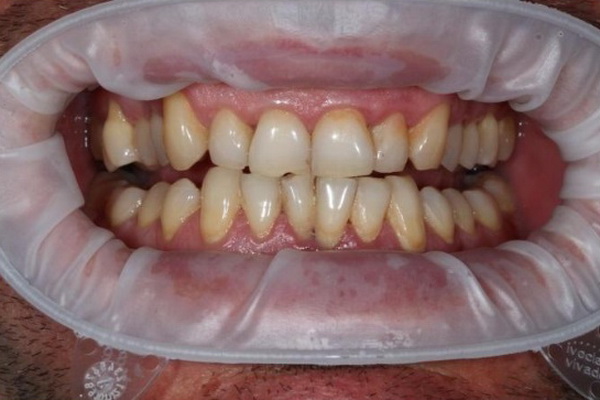

Стан ясен та зубів через 8 місяців після лікування (до та після проведення планової професійної гігієни ротової порожнини).